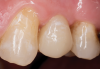

Fig 3. After endodontic treatment, crown lengthening was performed to develop an ideal ferrule effect.

Figure 3

Fig 4. An adequate collar effect of 2 mm of sound tooth structure would provide an anti-rotational feature for the stability of the crown.

Figure 4

Fig 5. Buccal view of optimal ferrule effect with a healthy biological framework.

Figure 5

After completion of the endodontic treatment and crown lengthening to develop an ideal ferrule effect (Figure 3 through Figure 5) a diagnostic wax-up was fabricated to an ideal coronal preparation geometric shape, dimension, and height for the anticipated final composite core buildup (Figure 6). A clear polyvinyl siloxane (PVS) impression material was injected into a nonperforated tray, placed over the diagnostic wax-up, and then put into a pressure pot with cold water for 5 minutes. This procedure is aimed at reducing the potential for the formation of voids and bubbles in the impression material (Figure 7 and Figure 8). A small opening was made above the tooth to be restored using a tapered diamond bur (6847) (Figure 9). It is important to clean the internal surfaces with a microbrush to prevent silicone debris from integrating into the flowable material. Prior to the restorative procedure, a diagnostic wax-up was fabricated to the anticipated extracoronal contours for development of the final crown (Figure 10).